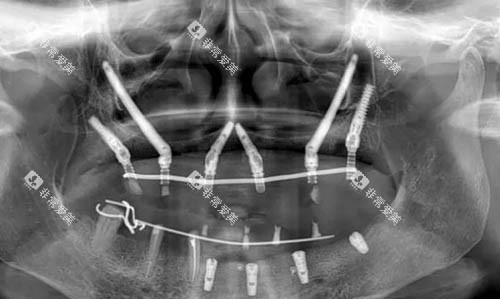

1.临床实例

某患者因长期佩戴假牙导致上颌骨重度萎缩,传统种植方案需大量植骨。

采用穿颧穿翼种植技术后,医生在颧骨和翼板区植入4颗种植体,成功修复半口牙齿。术后患者即刻安装临时修复体,咀嚼功能改善良好。